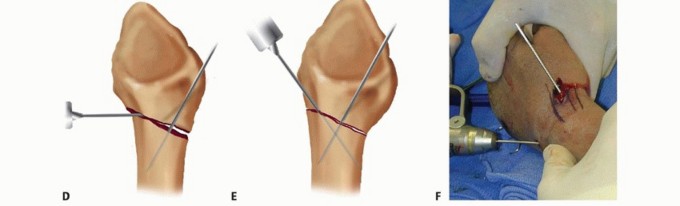

KAPANDJI TECHNIQUE FOR PERCUTANEOUS PINNING

TECH FIG 2 • A. An incision is made over the radial styloid, and a K-wire is manually inserted into the fracture site. B. The wire is levered distally to correct the radial inclination. C. The wire is advanced proximally, using power, into cortical bone. D. An incision is made over Lister tubercle, and a wire is inserted into the fracture site. E,F. The wire is levered distally to correct the dorsal angulation and advanced proximally using power into cortical bone.